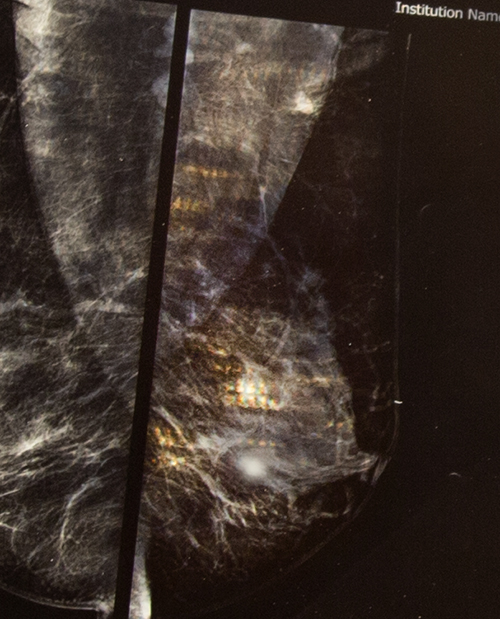

Even among all the moments which there is full of darkness, emptiness and nowhere ... , still some spot light of hopes can be find .. ( The story behind: She had cancer , but golden hopes could be find in her vessels , she was a fighter)